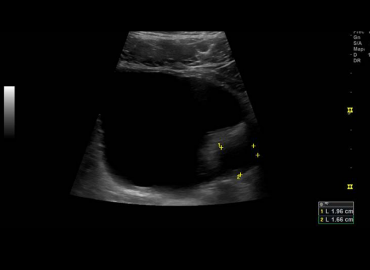

Dolor en FID y Leucocitosis.